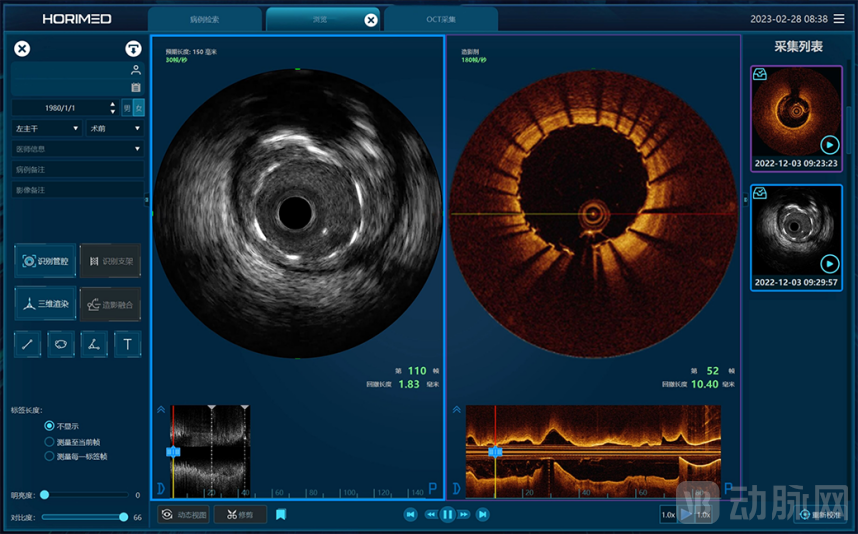

恒宇医疗将OCT&IVUS技术融合,双模一体,革新应变。心眸GEMISIGHT具备OCT&IVUS两个独立运行的模块,配备了双马达和双导管系统。继承了单一OCT和IVUS优秀的参数,在不牺牲各自参数和性能时,灵活切换应对多种病变。OCT&IVUS可以更好衔接进行工作,使冠心病的诊治更加精准高效,真正满足临床个性化需求。

天津恒宇医疗成立于2016年,专注于血管内超声(Intravascular Ultrasound, IVUS)设备及导管、光学相干断层成像(Optical Coherence Tomography, OCT)设备及导管、IVUS/OCT一体机式的双导管系统、基于IVUS和OCT的无创血流储备分数(Fractional Flow Reserve, FFR)平台、融合OCT与近红外光谱(Near-Infrared Spectroscopy, NIRS)的单光源双模态OCT-NIRS技术及血管内激光斑块消蚀技术的自主研发、生产和销售,掌握光学、超声及导管平台技术,并不断基于底层技术进行全球领先的创新,致力于为医患提供以影像类产品为基础的泛血管一体化解决方案。